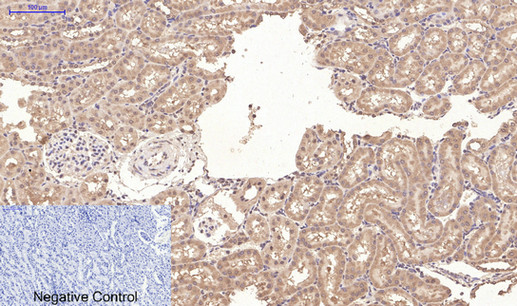

Immunohistochemistry analysis of paraffin-embedded rat kidney tissue using CD10 antibody.High-pressure and temperature Sodium Citrate pH 6.0 was used for antigen retrieval. Negative control was used by secondary antibody only.